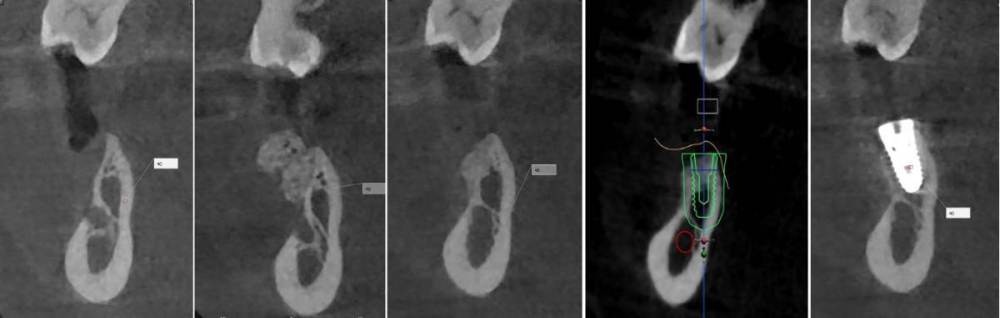

kramer Опубликовано 26 июня, 2023 Поделиться Опубликовано 26 июня, 2023 Первые три снимка в каждом ряду это до, сразу после, через 3 месяца? Ссылка на комментарий

karasov Опубликовано 26 июня, 2023 Автор Поделиться Опубликовано 26 июня, 2023 8 минут назад, Женька сказал: что за магия вне Хогвартса и как это держится?) у ТЛ осстем набор и имплантоводы подходят под хирургический шаблон?? Или мукотом и вслепую без шаблона? Вертикальный разрез кпереди от дефекта, отслаивание слизисто-надкостничного лоскута тупо кзади от разреза, введение в него шприцом графта, два шва. Графт введен вслепую с избытком-позже он лизировался,что видно на кт. SS устанавливаю стандартным набором oneguide, докручиваю имплантоводом от SS. 1 час назад, kramer сказал: Первые три снимка в каждом ряду это до, сразу после, через 3 месяца? До,сразу после, через 3 месяца, планирование, контроль Ссылка на комментарий